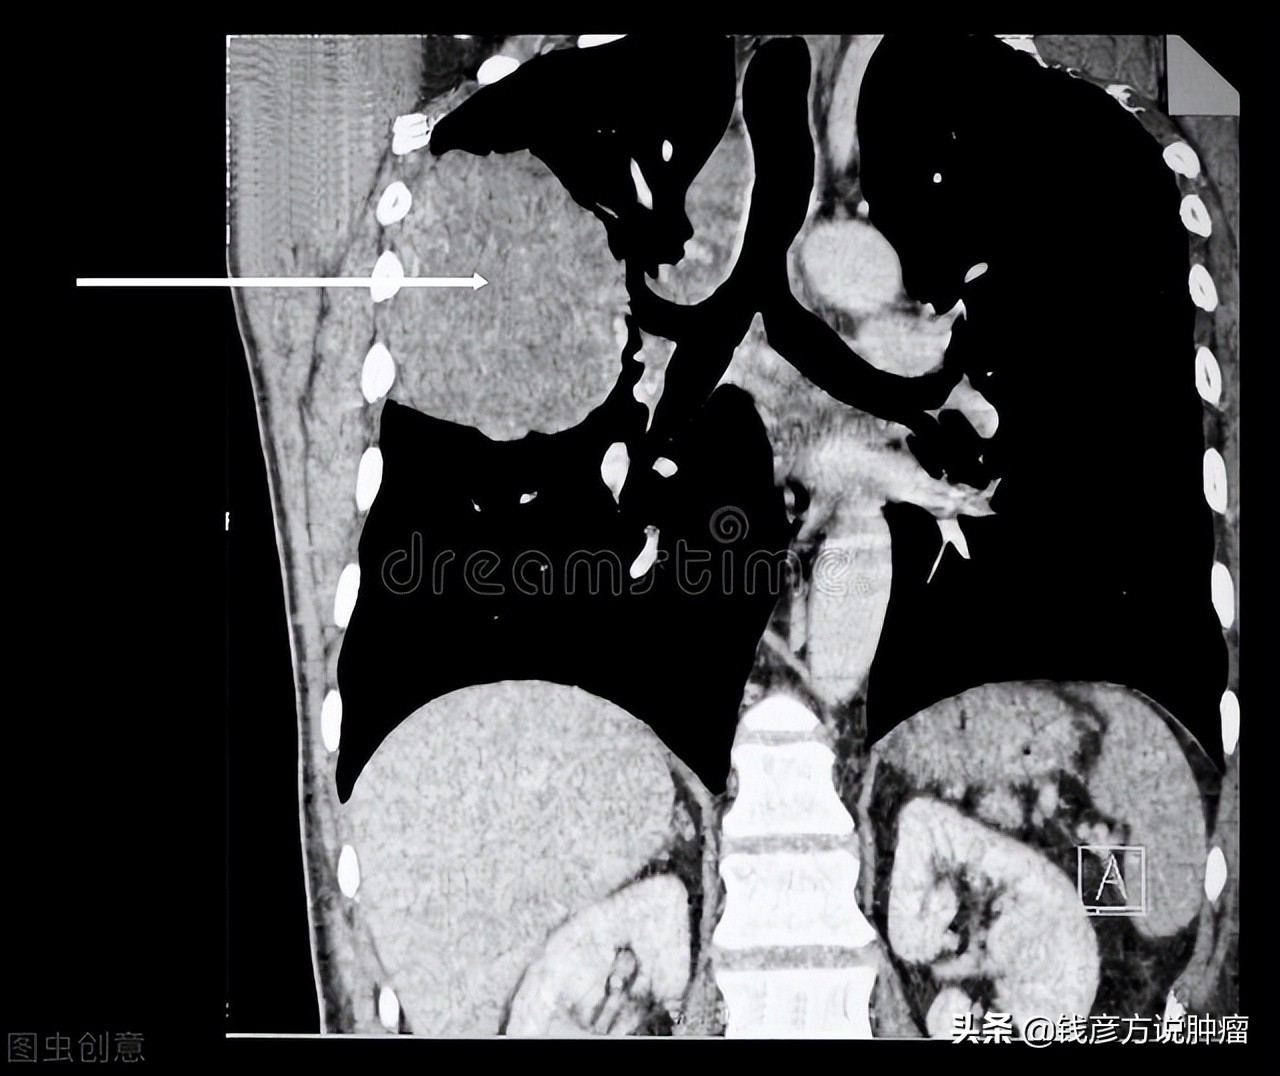

家属:老人得恶性肿瘤晚期(肺癌),75岁,很苦恼,是给老人化疗还是放弃治疗,急得没了主意,希望得到专家的指点

这位先生他已经75岁了,得了晚期肿瘤,也就是说不在原位了,也可能涉及到远处,涉及到骨、涉及到脑、涉及到淋巴,这种情况下病灶比较多,全身都有,这种情况下进行化疗确实承受不了,因为全身化疗它本身*伤杀**力很大,放疗、化疗同样作用;